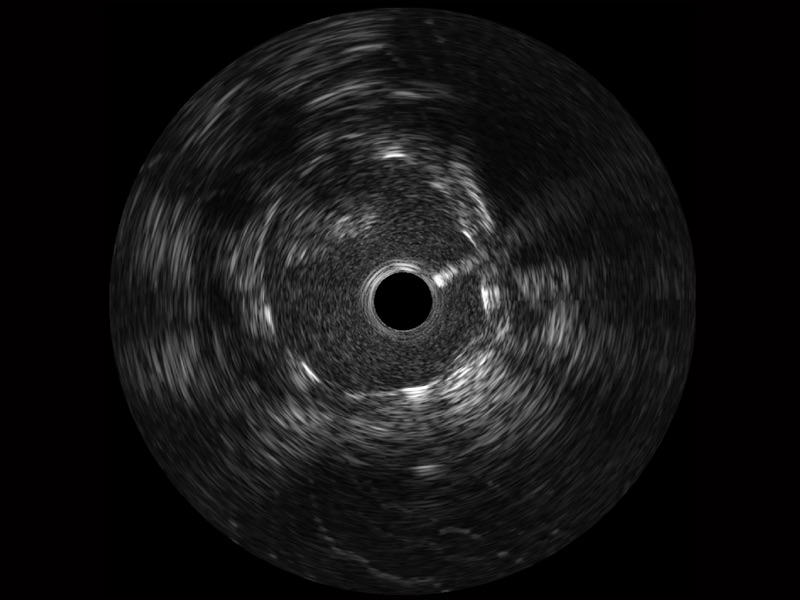

• DB中国旗舰官方网站宽频IVUS图像

• 传统IVUS图像

对比传统IVUS导管成像,DB中国旗舰官方网站宽频IVUS图像的近场支架梁显影更细腻,远场中膜外血管仍清晰可辨,兼顾远中近,兼顾分辨力与穿透深度